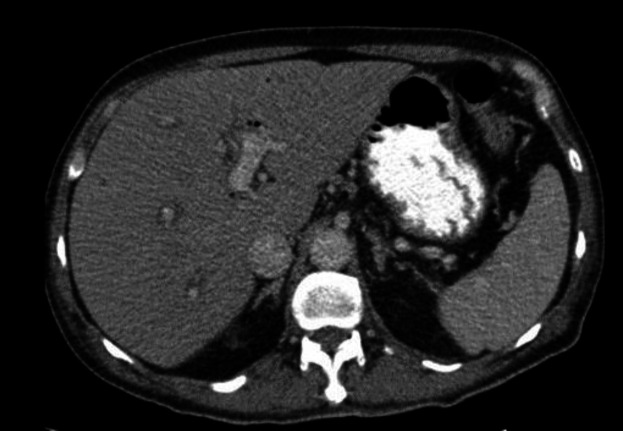

Vital sign revealed blood pressure 90/60 mmHg, body temperature 38.5 ºCelsius degree and heart rate 110/min. Physical examination demonstrated tenderness in RUQ and Murphy’s sign was positive. The laboratory findings have shown in table 1. With the possibility of cholangitis, he was admitted and initial management include bowel rest, IV fluid hydration and IV antibiotics were started. An abdominal ultrasound (US) demonstrated contracted gallbladder with extrahepatic and intrahepatic dilated ducts and a dilated common bile duct (10mm). The CT scan was done and showed evidence of pneumobilia in biliary ducts (figure 1). He underwent emergent endoscopic retrograde cholangiopancreatograph (ERCP) and sten placement without sphincterotomy due to low platelet count and high INR level. In ECRP, papilla was edematous and one supra-papillary fistula (spontaneous) were seen. Cannulation of CBD via fistula was done. CBD was 10mm and contained multiple filling defects. Dilatation with balloon TTS8-10 was done. Copious amount of sludge and small stones were extracted with balloon. One plastic stent 8mm was inserted complete drainage was seen.